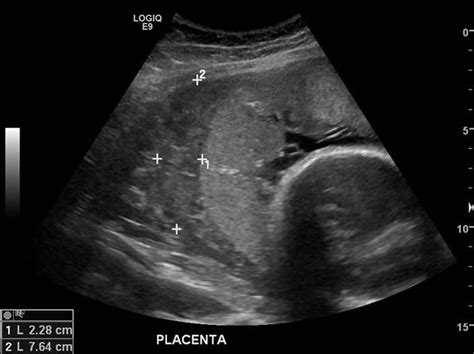

Diagnosing Placenta Previa

Placenta previa is usually diagnosed through an ultrasound. During the ultrasound, the healthcare provider can visualize the placenta’s position in relation to the cervix. If placenta previa is suspected, further ultrasounds may be required to monitor the condition.

Placenta previa is a condition where the placenta partially or completely covers the cervix, the opening of the uterus. This can lead to significant bleeding during pregnancy and childbirth. The condition is typically diagnosed during a routine ultrasound, and it can occur in about 1 in 200 pregnancies.